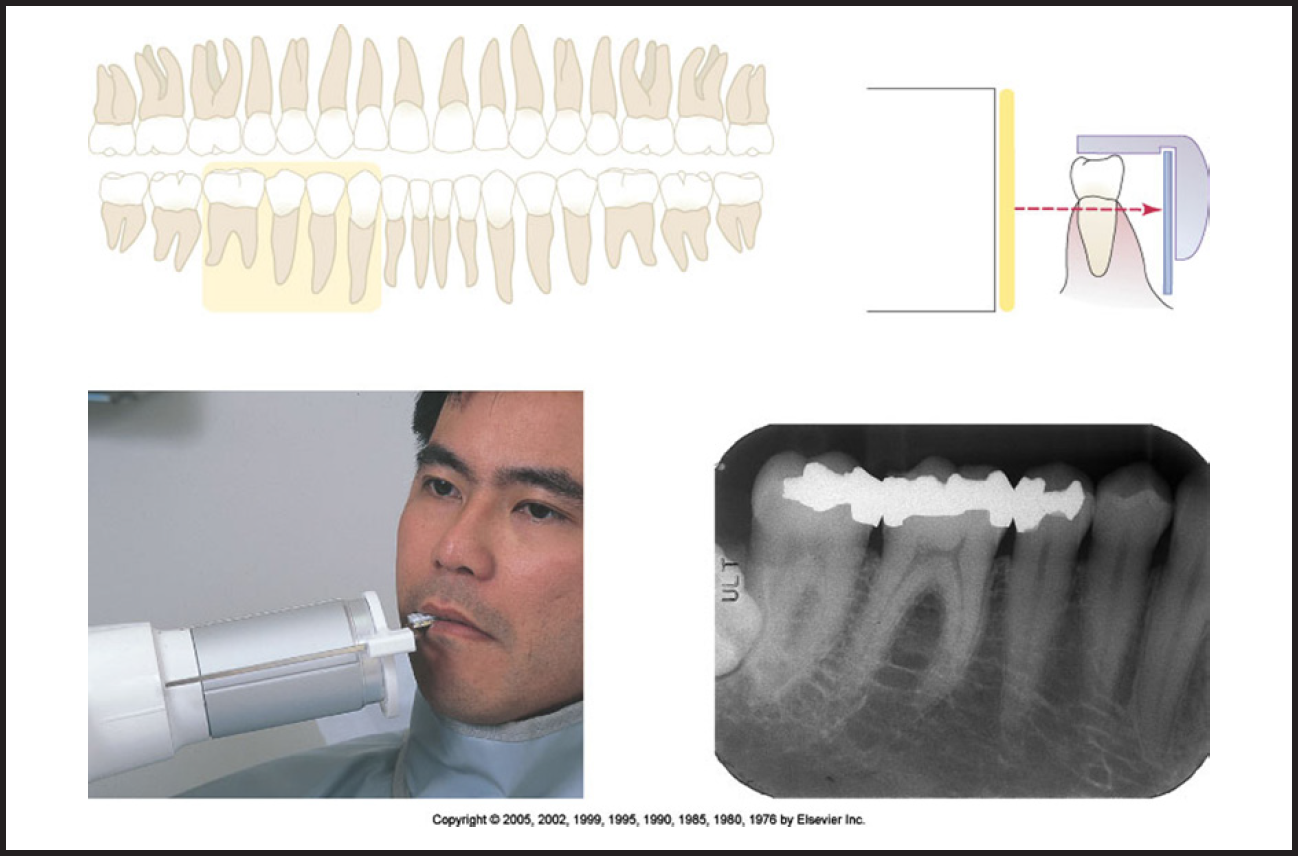

Bitewing images are parallel images because the receptor is positioned parallel to the long axis of the teeth and the beam is perpendicular to the receptor as in Figure 60. A bitewing tab is utilized to stabilize the receptor as the patient bites together.

Tube head position is illustrated in Figure 62, and a sample set of bitewing radiographic images is illustrated in Figure 63.

Figure 3 - Occlusal Images

Figure 3